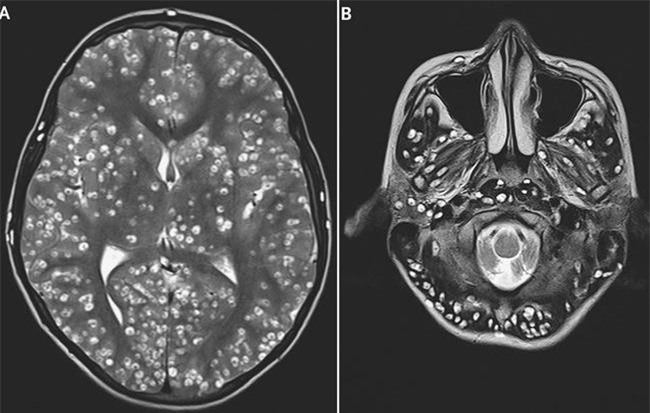

Người đàn ông 40 tuổi đến viện trong tình trạng đau đầu nhiều, buồn nôn, kèm theo sốt tăng dần, tê yếu nửa người phải. Kết quả citi sọ não cho thấy một ổ sán não khổng lồ ngụ ngay trong não.

Thịt lợn nhiễm nang sán nếu ăn phải sẽ ảnh hưởng lớn đến sức khỏe, thậm chí có thể bị động kinh, viêm não, mù mắt vì loại ký sinh trùng này.